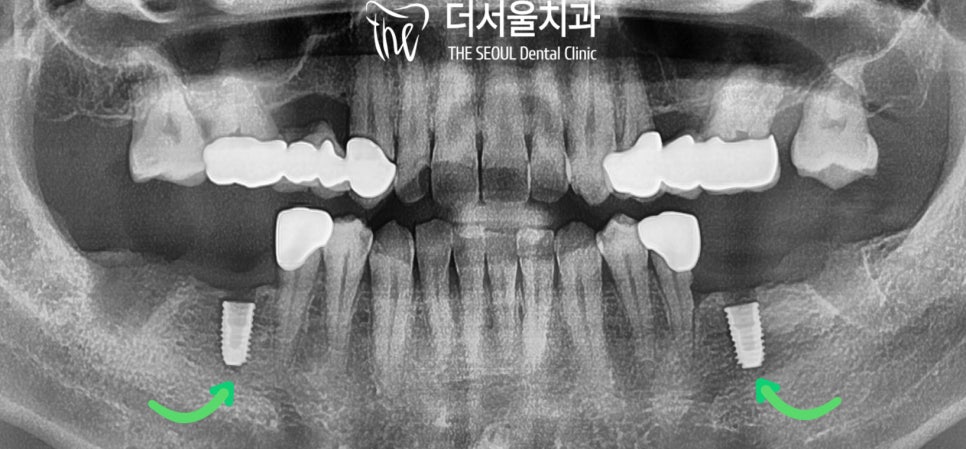

먼저 더 이상 기능을 못 하는

아래쪽 구치부를 발치했습니다.

그리고 잇몸 속에 있는 염증도 깨끗하게 제거하고

여러번 소독하여 회복이 이뤄지도록 하였습니다.

멀리서 오신 만큼 #36, #46을 먼저 식립하여

임시치아로 식사를 가능하게 해드렸습니다.

그리고 많은 데이터로 만들어진

가이드에 맞춰 계획했던 위치에 오차 없이

픽스처를 꼼꼼하게 심어줬습니다.